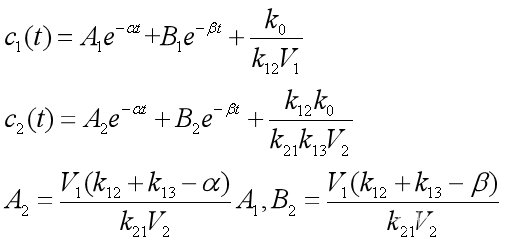

3、口服或肌肉注射

这种给药方式相当于在药物进入中心室以前,先有个将药物吸收入血液的过程,可以简化为一个吸收室,如图15所示,x0(t)是吸收室的药量,药物由吸收室进入中心室的速率为k01。

图15 详细的三房室模型

吸收室药量满足 【4.8】

【4.8】

将【4.8】代入 得到

得到 【4.9】

【4.9】

在【4.9】条件下,【3】的解为![]() 【4.10】

【4.10】

(设k01≠α,β),其中系数A,B,E由初值条件c1(0)=0,c2(0)=0确定。